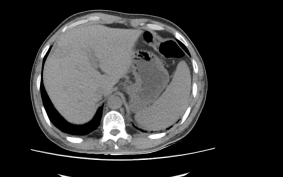

蔡##,男,53岁,2013.6.22因“1.直肠癌 2.右肝转移癌”入住我科,于2013.06.26行“CT引导下肝转移瘤射频消融术”,2013.06.27在全麻下行“腹腔镜下直肠癌切除术+横结肠造瘘术+左侧睾丸鞘膜翻转术”,术后病理PT4N2M1,术后恢复顺利,并予继续化疗等综合治疗,现定期门诊复查,未见复发转移,一般情况良好,生活质量高。

治疗前肝转移CT图片